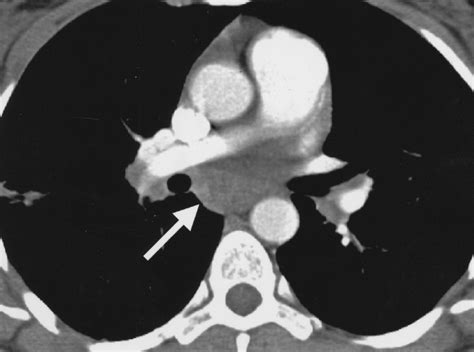

• Cardiovascular Imaging: Spiral CT Scans are used to visualize the heart and blood vessels, helping to diagnose conditions such as coronary artery disease, aneurysms, and heart valve problems.

• Cancer Detection: Spiral CT Scans are instrumental in detecting and staging cancer, particularly in the lungs, liver, and other organs. The detailed images help in identifying tumors and assessing their size and location.

• Trauma Imaging: In emergency situations, Spiral CT Scans provide quick and accurate imaging of injuries, including fractures, internal bleeding, and organ damage.